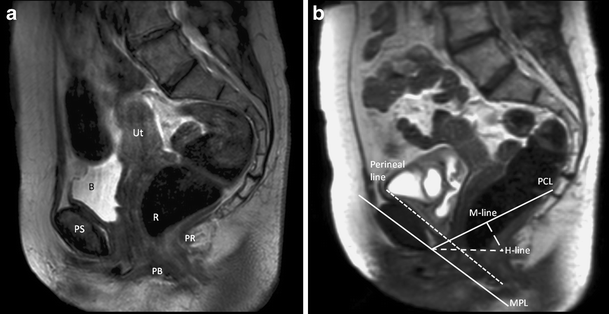

a Static T2-weighted turbo spin echo (TSE) at rest for anatomical reference in midsagital plane through the pelvis of a 66-year old woman with pelvic organ prolapse (POP) symptoms. The uterus (Ut), bladder (B), pubic symphysis (PS), rectum (R), puborectal muscle (PR), and perineal body (PB) are shown. b Dynamic midsagital half-Fourier-acquisition single-shot turbo spin-echo (HASTE) sequence during straining in the same patient. Reference lines: pubococcygeal line (PCL), H-line, perineal line, midpubic line (MPL), and M-line